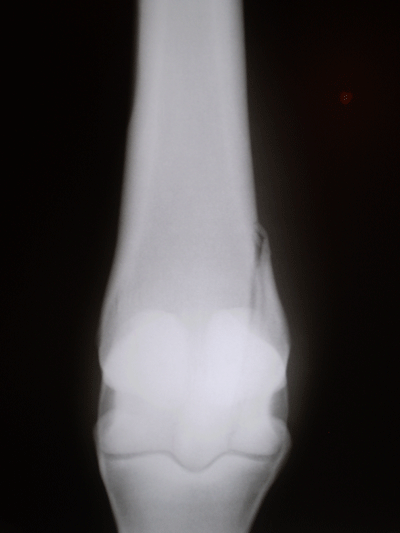

CIRURGIAS

Cirurgias abdominais, de tecido mole, ortopédicas, incluindo vídeo-artroscopia e  reparo de fratura em ossos longos

EXAMES DE IMAGEM

Ultrassonografias em geral, radiologia digital, endoscopia em estação e dinâmica (durante exercício) e gastroscopia